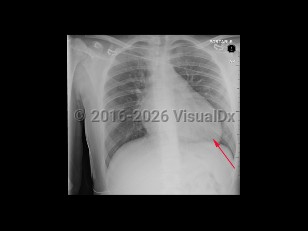

Imaging Studies image of Hypertrophic cardiomyopathy - imageId=8359232. Click to open in gallery.  caption: '<span>AP view of the chest demonstrating an enlarged heart in this patient with diagnosed hypertrophic cardiomyopathy.</span>'

AP view of the chest demonstrating an enlarged heart in this patient with diagnosed hypertrophic cardiomyopathy.